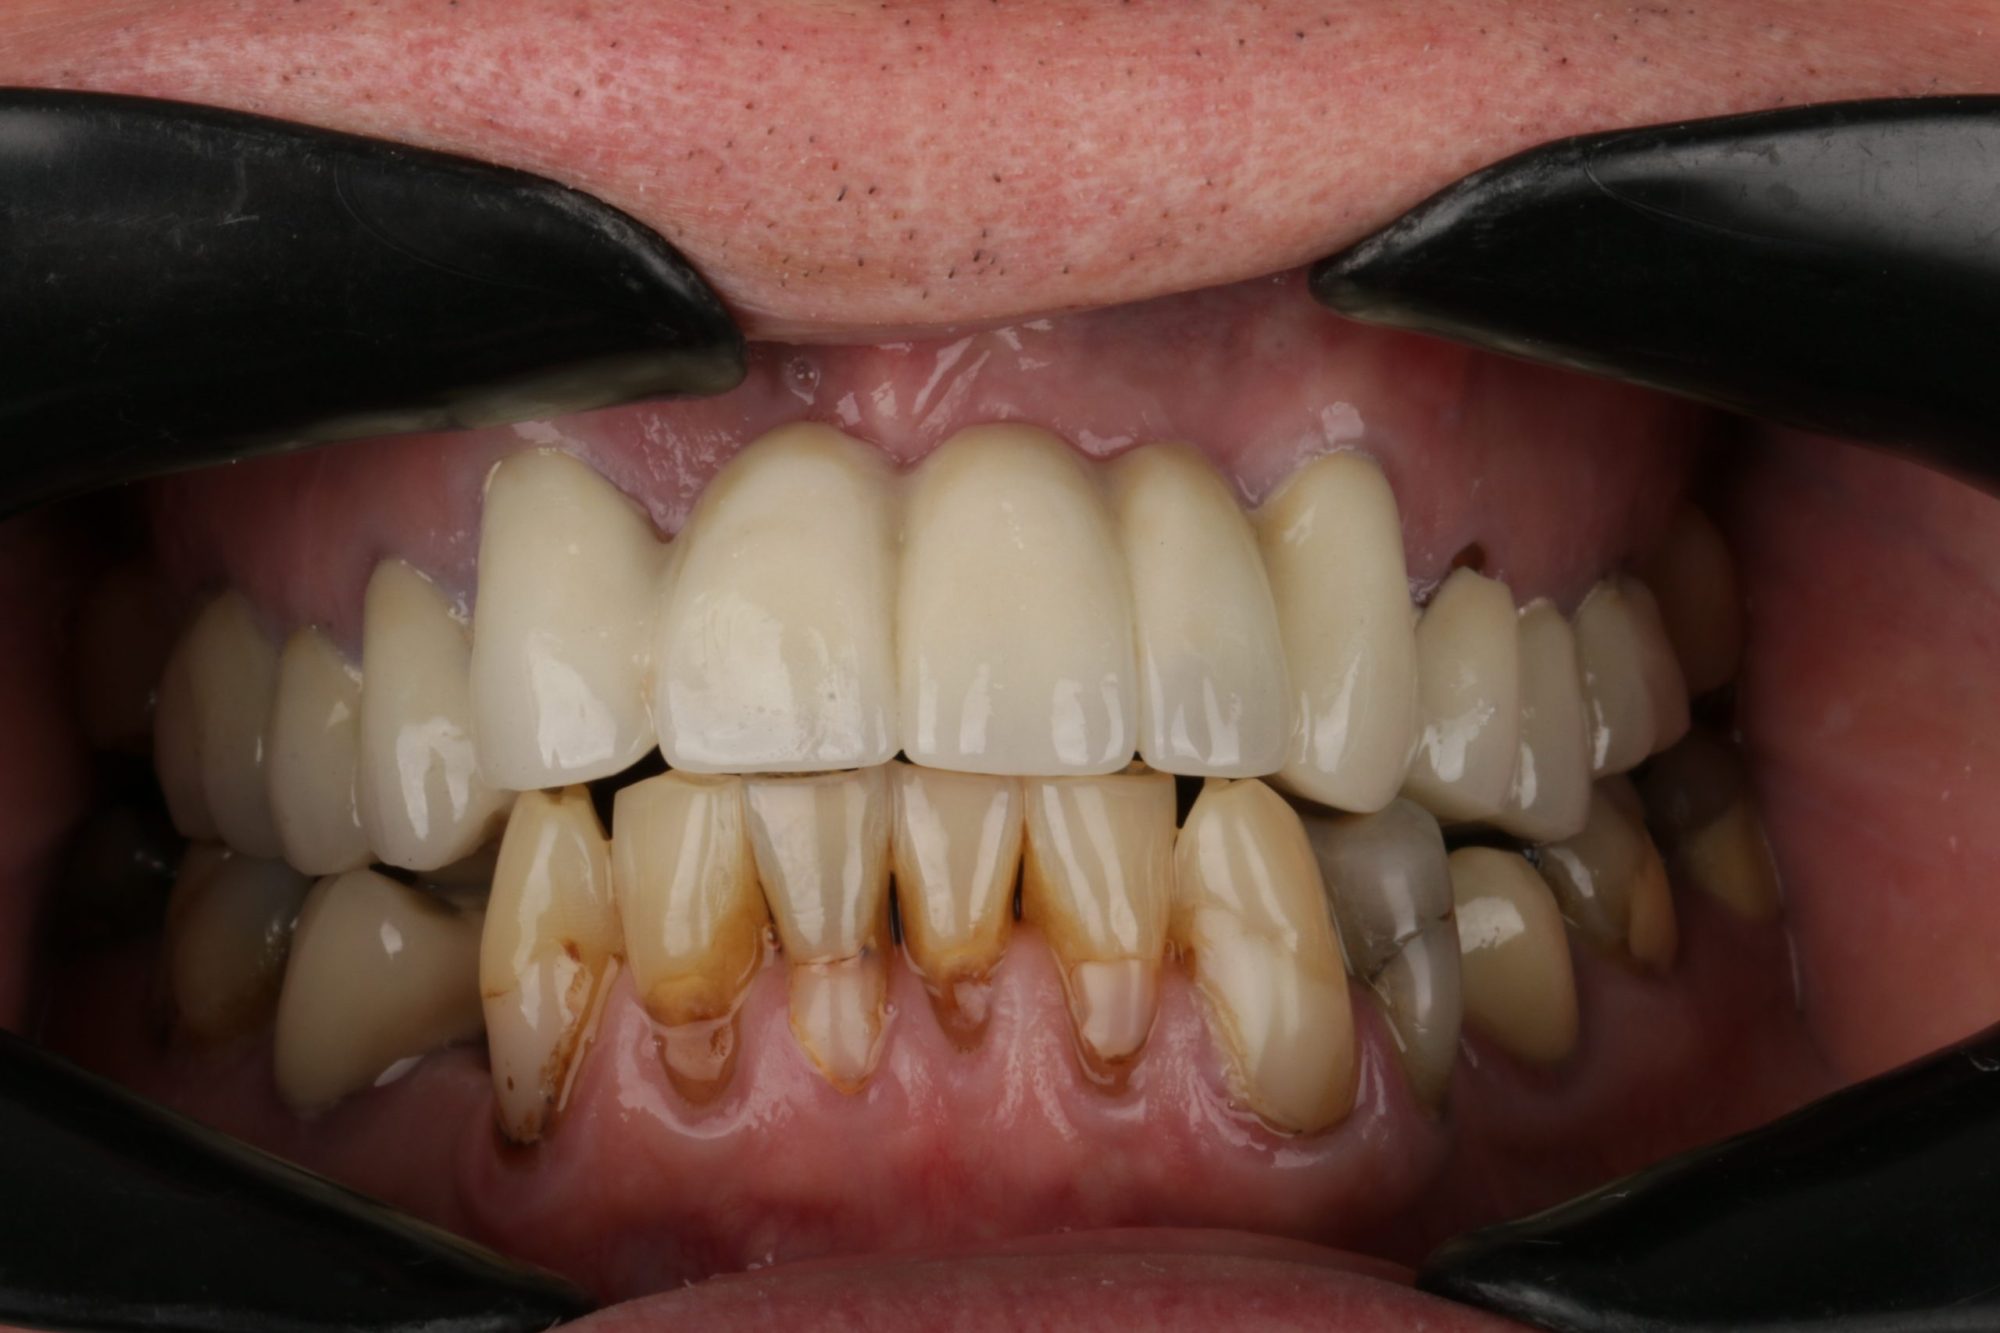

A 75-year-old gentleman was referred to Renovo Dental for an endodontic consultation.  He had undergone several root canal treatments (RCTs) with mixed outcomes. His 12-unit upper metal ceramic crown (MCC) bridge was loose and had been temporarily cemented. Its long-term prognosis was poor (Figure 1).